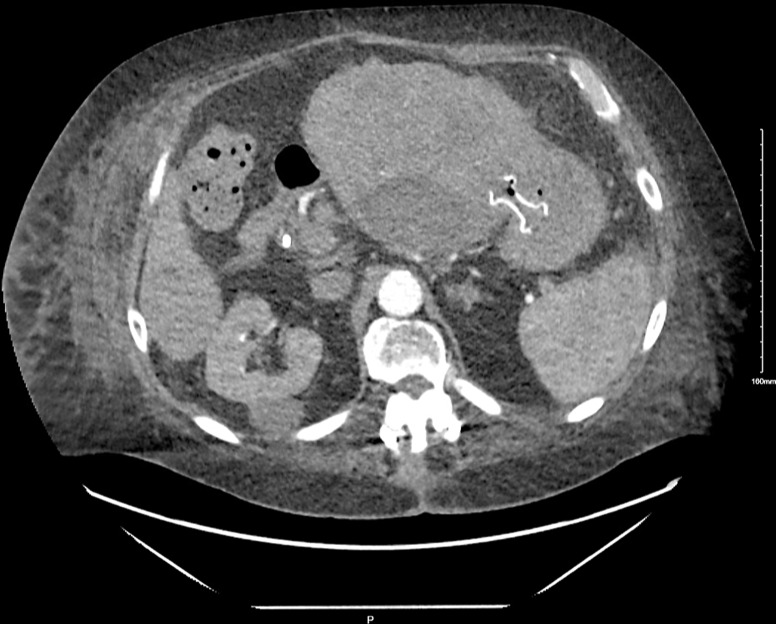

Case presentation: Three patients, average age 75 years (two men, one woman), underwent EUS-guided drainage using LAMS for an infected liver cyst, infected liver hematoma within a hepatocellular carcinoma lesion, and a symptomatic simple liver cyst, respectively. All the hepatic fluid collections were in the left hepatic lobe and had an average diameter of 11 centimeters (cm). Only the female patient with a symptomatic cyst had prior percutaneous drainage. Successful LAMS placement was achieved in all cases. Clinical success, defined as cyst resolution or significant size reduction, was observed in all patients. The superinfected liver cyst showed complete resolution, yet the stent remained in place as the patient transitioned to hospice and subsequently passed away. In the case of the superinfected liver hematoma, the stent was removed after 2 months. No recurrence was observed in follow-up imaging 8 months later, and the patient passed away. The symptomatic simple liver cyst patient had the stent removed 15 months later, with no recurrence in imaging 11 months of post-stent removal.

Conclusion: EUS-guided LAMS placement emerges as a less invasive and viable option for treating symptomatic and/or infected hepatic fluid collections compared to surgery or percutaneous drainage. While it may be a preferable choice in institutions with the requisite expertise, further studies are essential to establish its definitive role as a first-line intervention.